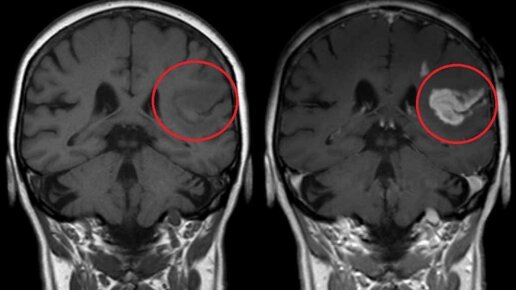

Проведение компьютерной томографии с контрастом и без позволяет на раннем этапе диагностировать заболевания органов брюшной полости и малого таза, грудной клетки, всех отделов позвоночника, верхних и нижних конечностей, головного мозга...

КТ с контрастом – это современный способ обследования, применяемый в целях обнаружения различных нарушений в функционировании внутренних органов. Такую диагностику применяют для выявления патологий в головном мозге, брюшной полости, легких. Что такое КТ с контрастом Компьютерная томография с контрастированием является самым эффективным способом оценки состояний сосудов и полых органов. Диагностика выполняется на современном оборудовании, представляющем собой мощные томографы. Для повышения четкости снимков прибегают к контрастированию...